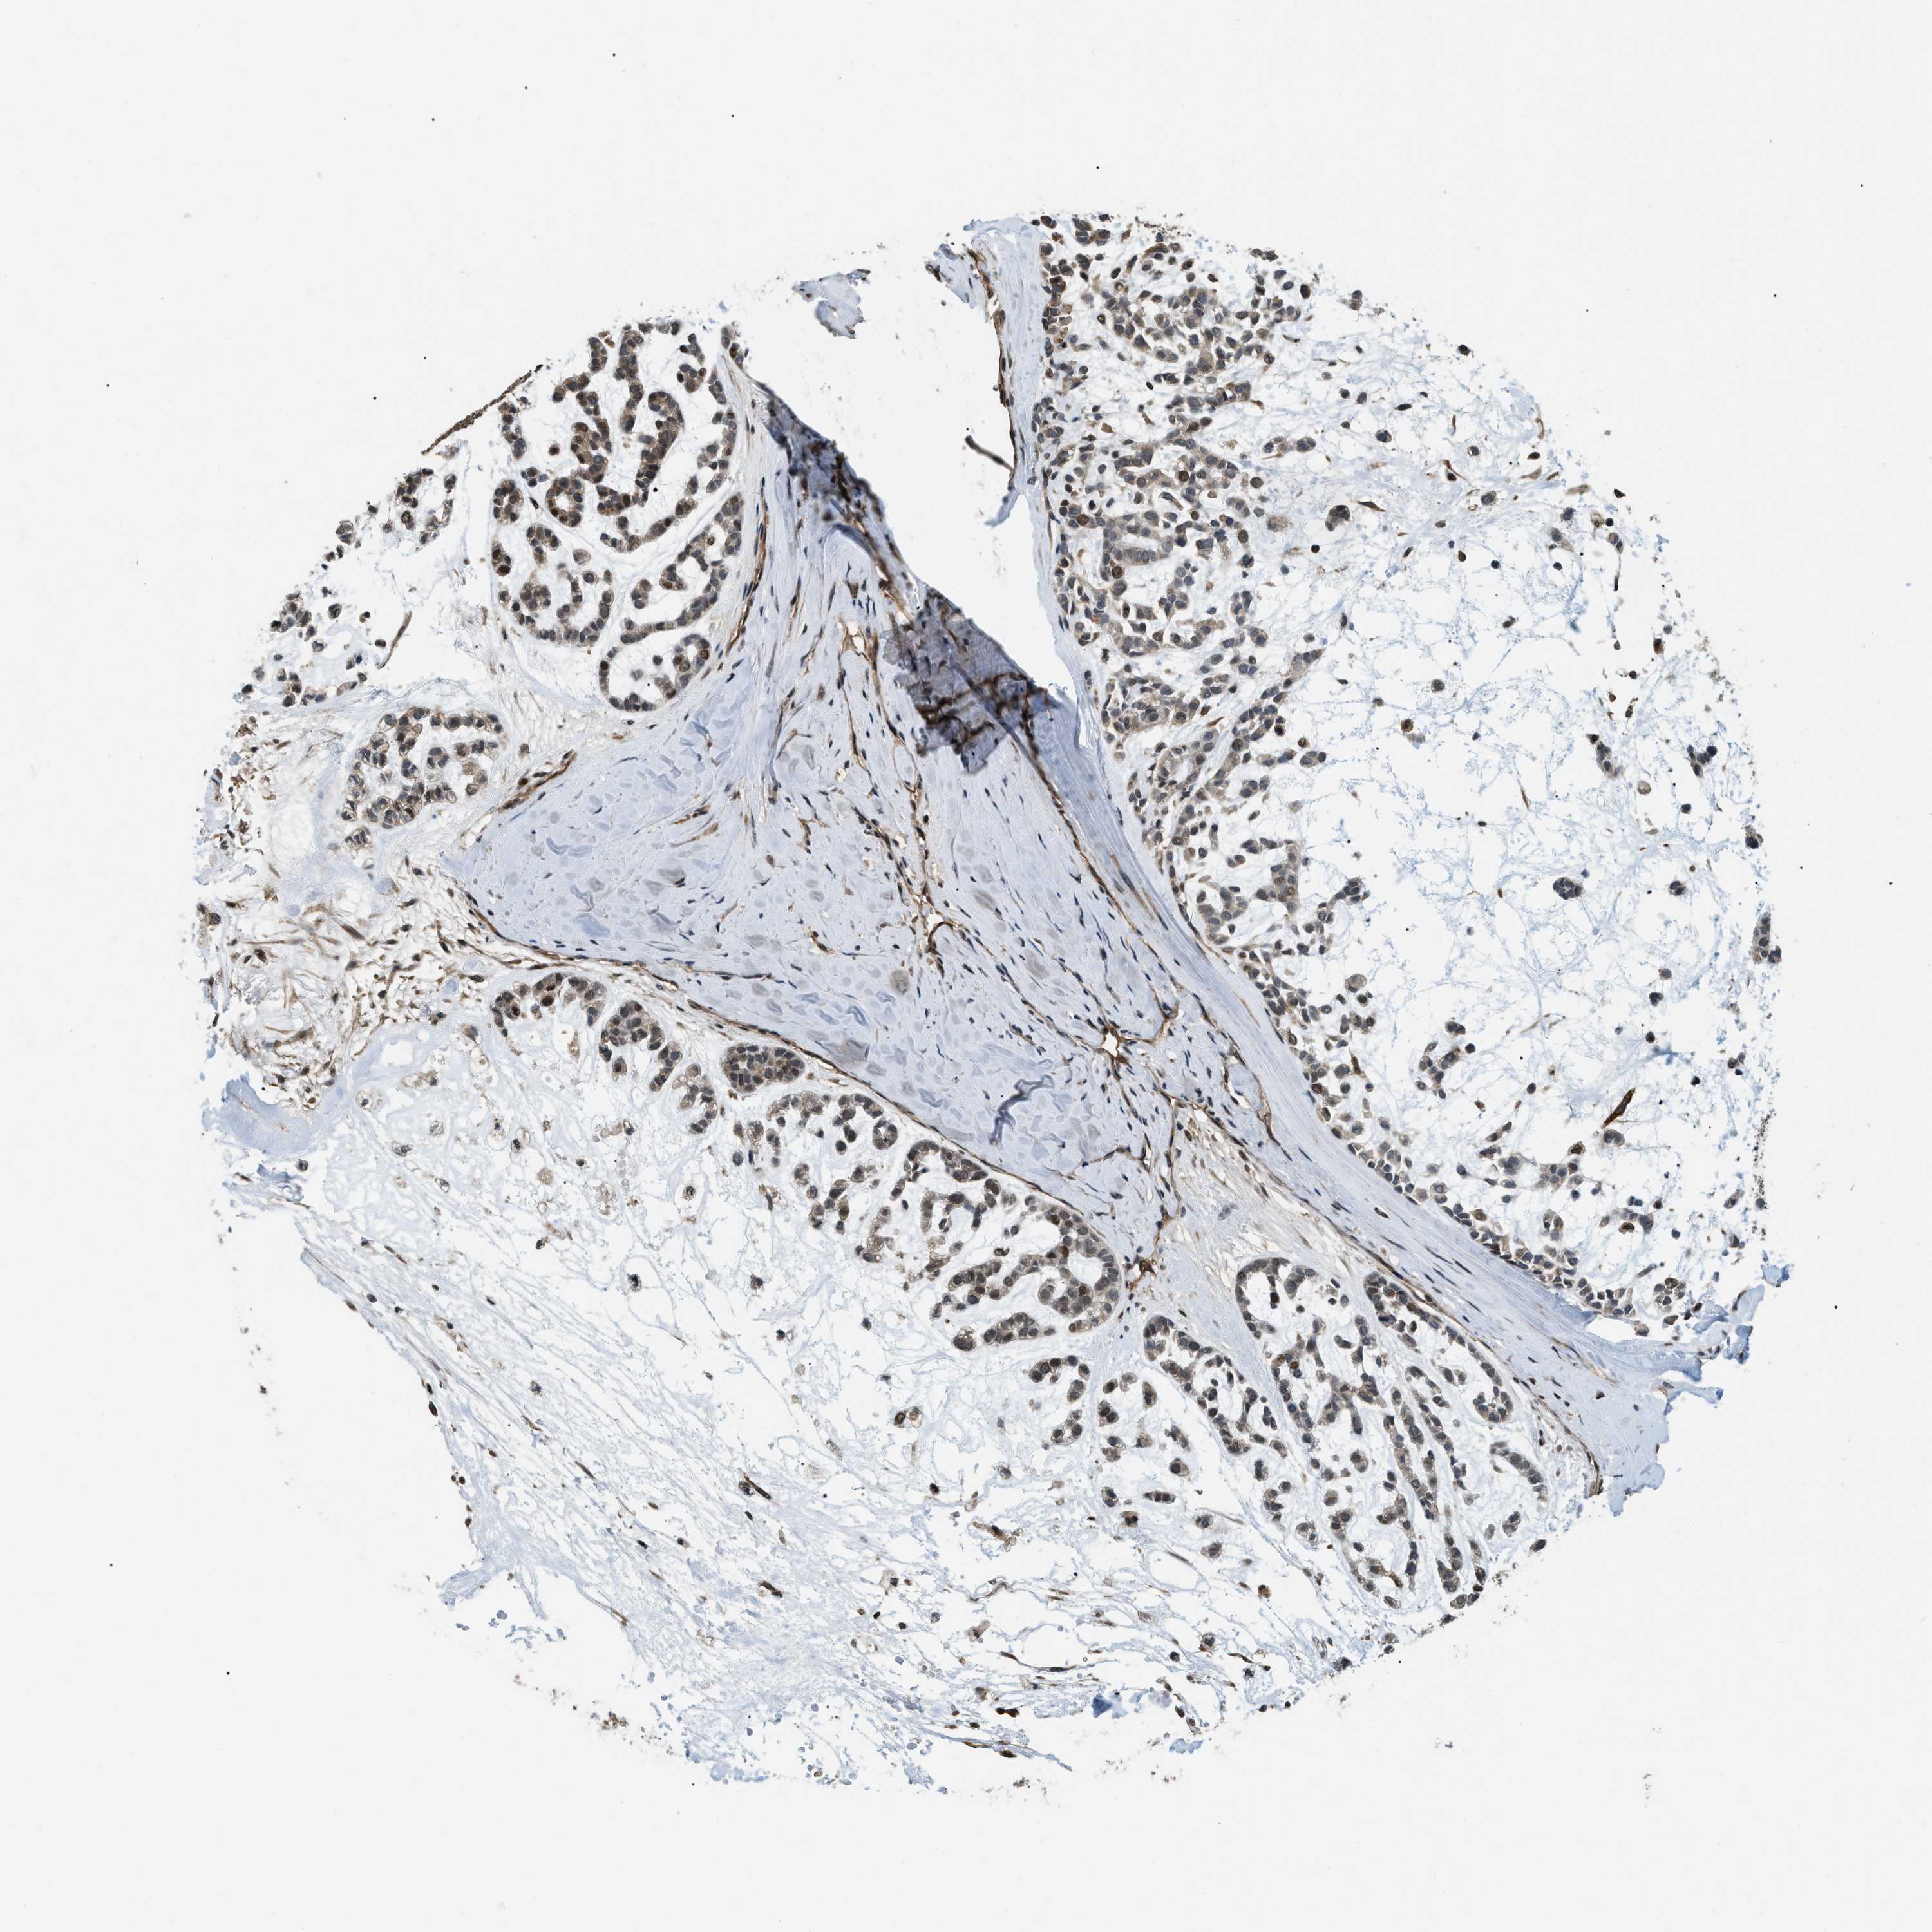

HEAD AND NECK CANCER - Protein expressioni

A mouse-over function shows sample information and annotation data. Click on an image to view it in a full screen mode. Samples can be filtered based on level of antibody staining by selecting one or several of the following categories: high, medium, low and not detected. The assay and annotation is described here.

Antibody stainingi

Antibody staining in the annotated cell types in the current human tissue is reported as not detected, low, medium, or high, based on conventional immunohistochemistry profiling in selected tissues. This score is based on the combination of the staining intensity and fraction of stained cells.

Each image is clickable and will lead to virtual microscopy that enables deeper exploration of all samples and also displays staining intensity scores, fraction scores and subcellular localization as well as patient and tissue information for each sample.

Antibody HPA008399

Squamous cell carcinoma, NOS